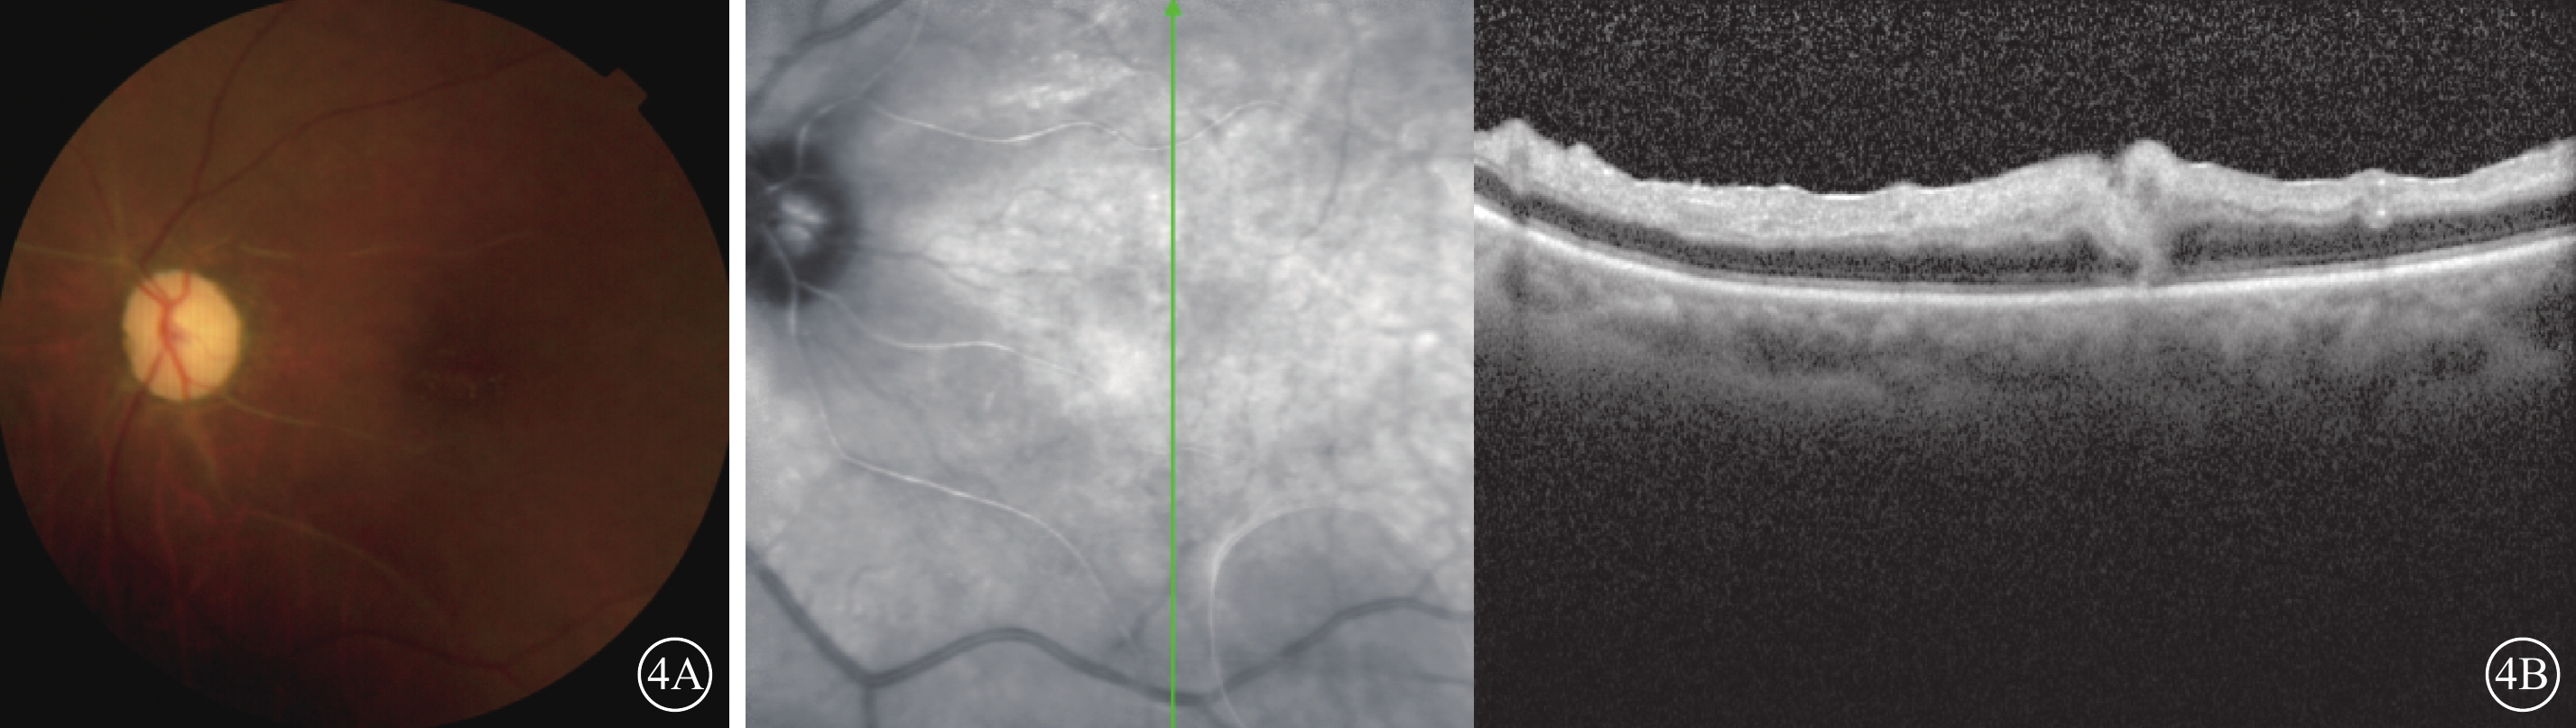

治療:手術后第2天因左眼黑矇,立即給予硝酸甘油500 μg舌下含服,吸氧,球后注射罌粟堿30 mg,同時全身擴容、擴血管、降眼壓、抗凝、神經營養及甲基強的松龍沖擊等治療。手術后第4天,患者自覺左眼視物發黑轉為發紅,但視力檢查仍無改善。手術后第35天復診,眼底視盤邊界清楚,顏色蒼白;視網膜水腫減輕,黃斑高度隆起減輕,視盤鼻側羽毛狀灰白色病灶轉淡,部分視網膜血管呈白線狀(圖4A)。OCT檢查,視網膜內層水腫減輕,層次仍不清晰,黃斑中心凹處橢圓體帶無恢復(圖4B)。

左眼手術后第35天彩色眼底、OCT像。4A示彩色眼底像,視盤顏色蒼白,鼻側羽毛狀灰白色病灶轉淡;視網膜水腫減輕,部分視網膜血管呈白線狀。4B示OCT像,左圖為掃描部位和方向,右圖為檢查結果。黃斑區視網膜內層水腫減輕,但層次仍不清晰,黃斑中心凹處橢圓體帶無恢復

左眼手術后第35天彩色眼底、OCT像。4A示彩色眼底像,視盤顏色蒼白,鼻側羽毛狀灰白色病灶轉淡;視網膜水腫減輕,部分視網膜血管呈白線狀。4B示OCT像,左圖為掃描部位和方向,右圖為檢查結果。黃斑區視網膜內層水腫減輕,但層次仍不清晰,黃斑中心凹處橢圓體帶無恢復

治療:手術后第2天因左眼黑矇,立即給予硝酸甘油500 μg舌下含服,吸氧,球后注射罌粟堿30 mg,同時全身擴容、擴血管、降眼壓、抗凝、神經營養及甲基強的松龍沖擊等治療。手術后第4天,患者自覺左眼視物發黑轉為發紅,但視力檢查仍無改善。手術后第35天復診,眼底視盤邊界清楚,顏色蒼白;視網膜水腫減輕,黃斑高度隆起減輕,視盤鼻側羽毛狀灰白色病灶轉淡,部分視網膜血管呈白線狀(圖4A)。OCT檢查,視網膜內層水腫減輕,層次仍不清晰,黃斑中心凹處橢圓體帶無恢復(圖4B)。

圖4

左眼手術后第35天彩色眼底、OCT像。4A示彩色眼底像,視盤顏色蒼白,鼻側羽毛狀灰白色病灶轉淡;視網膜水腫減輕,部分視網膜血管呈白線狀。4B示OCT像,左圖為掃描部位和方向,右圖為檢查結果。黃斑區視網膜內層水腫減輕,但層次仍不清晰,黃斑中心凹處橢圓體帶無恢復

圖4

左眼手術后第35天彩色眼底、OCT像。4A示彩色眼底像,視盤顏色蒼白,鼻側羽毛狀灰白色病灶轉淡;視網膜水腫減輕,部分視網膜血管呈白線狀。4B示OCT像,左圖為掃描部位和方向,右圖為檢查結果。黃斑區視網膜內層水腫減輕,但層次仍不清晰,黃斑中心凹處橢圓體帶無恢復